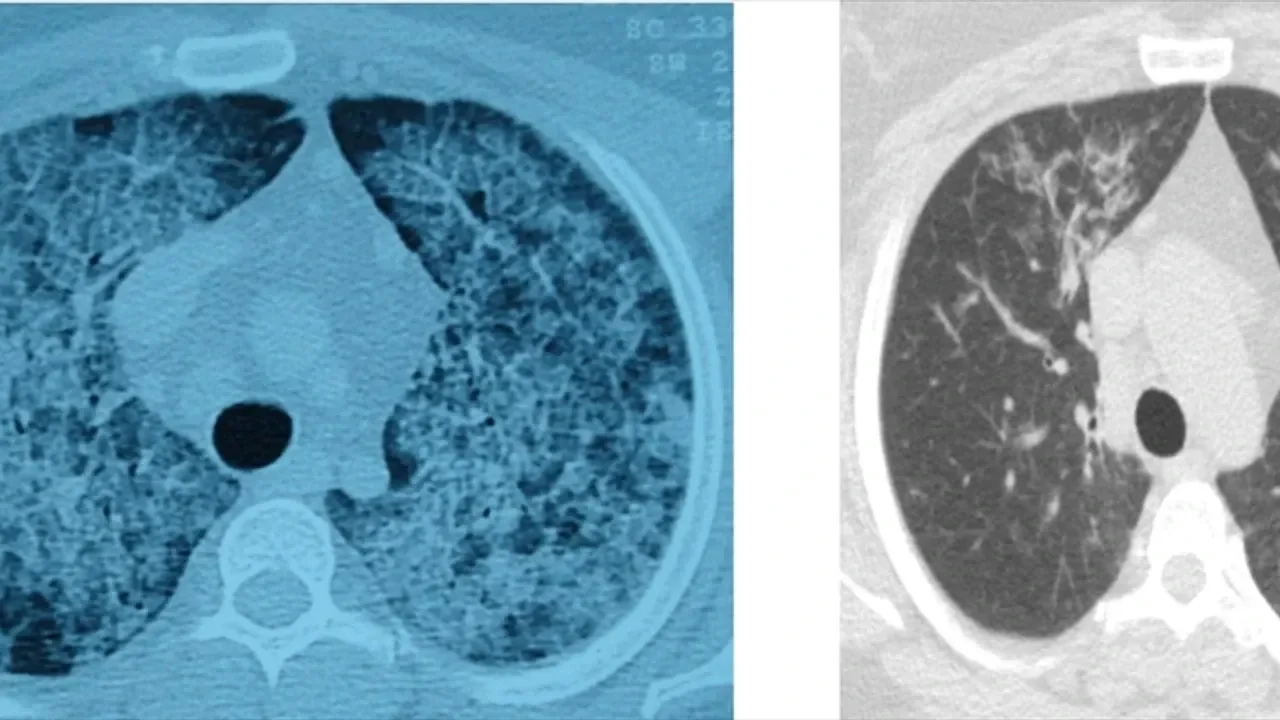

Hastalığın, kişinin kendi yağ ve proteinlerinin temizlenmesiyle görevli hücrelerdeki sorun nedeniyle akciğerlerdeki hava keseciklerinin birikmesi sonucu ortaya çıktığını aktaran Ergur, belirtilerin nefes darlığı, yorgunluk ve aşırı halsizlik olduğunu kaydetti.

Ergur, hastalığın çoğu zaman astımla karıştırıldığını, tanının ancak ileri tetkiklerle konulabildiğini ifade etti.

"Bazı hastalar kendiliğinden düzelirken bazen yalnızca tek ya da birkaç yıkama yetebilmekte, nadiren sürekli birikim olması nedeniyle akciğer yıkamalarının tekrarlanması gerekebilmektedir. Bu durumda hastaların yeniden nefeslerine kavuşabilmeleri, deneyimli ekibin bu tedaviyi uygulaması sayesinde olabilmektedir. Yıkama esnasında başta koyu olan, beklediğinde şişenin dibinde çökelti oluşan yıkama sıvısının rengi giderek açılmakta ve bu durumda yıkama işlemi sonlandırılmaktadır."